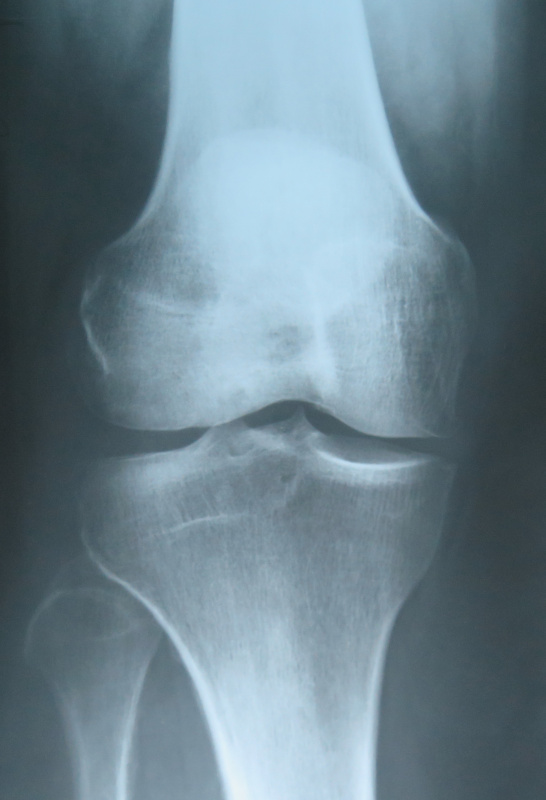

СУГЛОБ СКЛАДНИЙ. СУГЛОБОВА КАПСУЛА ТОНКА, УТВОРЮЄ БАГАТО СУМОК, ЯКІ СПОЛУЧАЮТЬСЯ ІЗ СУГЛОБОВОЮ ПОРОЖНИНОЮ. ЦЕ СПРИЯЄ ПЕРЕХОДУ ЗАПАЛЬНИХ ПРОЦЕСІВ (Є ДІАГНОЗ: БУРСИТ). ДЕ ВИ БАЧИТЕ ЦЕЙ СУГЛОБ.

варіанти відповідей

ЯКИЙ СУГЛОБ УТВОРЮЮТЬ ТАКІ КІСТКИ: FEMUR, FIBULA ТА TIBIA ?

КОЛІННИЙ С.

НАДП'ЯТКОВО-ГОМІЛКОВИЙ С.

ГОМІЛКОВО-СТОПНИЙ С.

НЕМАЄ ТАКОГО

ЛІКТЬОВИЙ С.

ПРОМЕНЕВО-ЗАП'ЯСТКОВИЙ С.

А ХІБА ТАКИЙ Є?

РОЗПІЗНАЙТЕ СКЛАДНИЙ СУГЛОБ, ЯКИЙ СКЛАДАЄТЬСЯ З ТРЬОХ КІСТОК, ОДНА З ЯКИХ РОЗТАШОВАНА В СУХОЖИЛКУ ЧОТИРИГОЛОВОГО М'ЯЗА СТЕГНА.